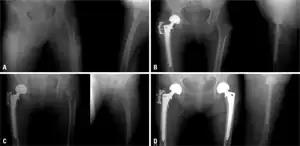

-

a) Initial radiographs of intertrochanteric fracture b) postoperative - bipolar hemiarthroplasty c) subsequent fracture in left femur neck d) radiograph after a bipolar hemiarthroplasty, the individual began medication for osteoporosis -

Conventional radiography is useful, both by itself and in conjunction with CT or MRI, for detecting complications of osteopenia (reduced bone mass; pre-osteoporosis), such as fractures; for differential diagnosis of osteopenia; or for follow-up examinations in specific clinical settings, such as soft tissue calcifications, secondary hyperparathyroidism, or osteomalacia in renal osteodystrophy. However, radiography is relatively insensitive to detection of early disease and requires a substantial amount of bone loss (about 30%) to be apparent on X-ray images.